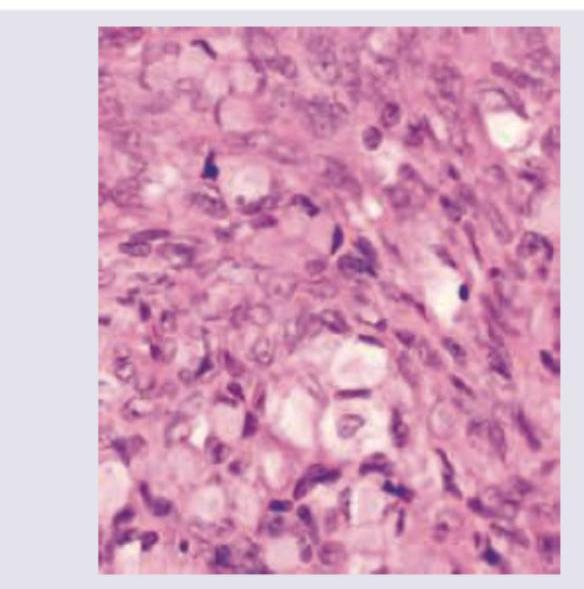

A 50 year old female presented with a breast mass that was operated and the microscopic examination in given. What is the diagnosis?

Explanation: ***Mucinous carcinoma breast*** - The micrograph shows clusters and nests of relatively uniform tumor cells floating in abundant extracellular **mucin**, which is the hallmark of this diagnosis. - This subtype of invasive ductal carcinoma is typically well-differentiated, hormone receptor-positive (**ER/PR positive**), and carries a more favorable prognosis than conventional invasive ductal carcinoma. *Lobular carcinoma breast* - This carcinoma is characterized by small, discohesive tumor cells infiltrating the stroma individually or in a **single-file** or **“Indian file”** pattern, which is not seen here [1]. - A key feature is the loss of **E-cadherin** expression, leading to the discohesive nature of the cells [3]. *Medullary carcinoma* - Histologically, this tumor presents as poorly differentiated cells arranged in solid, **syncytial sheets** with a prominent **lymphoplasmacytic infiltrate** [2]. - The image lacks both the syncytial growth pattern and the dense inflammatory background characteristic of medullary carcinoma [2]. *Phyllodes tumour* - This is a biphasic **fibroepithelial tumor**, characterized by a hypercellular stromal component and an epithelial component arranged in a **leaf-like** (phyllodes) architecture. - The defining feature is the proliferating stroma, whereas the image shows a carcinoma defined by its epithelial cells and extracellular mucin. **References:** [1] Cross SS. Underwood's Pathology: A Clinical Approach. 6th ed. Common Clinical Problems From Liver And Biliary System Disease, pp. 454-455. [2] Cross SS. Underwood's Pathology: A Clinical Approach. 6th ed. Common Clinical Problems From Liver And Biliary System Disease, pp. 455-456. [3] Kumar V, Abbas AK, et al.. Robbins and Cotran Pathologic Basis of Disease. 9th ed. The Breast, pp. 1068-1069.